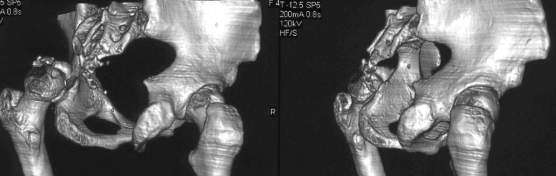

важаемые коллеги,пациент 23 лет (вес 75 кг), обратился к нам по поводу боли в тазобедренном суставе при ходьбе, нестабильность в нем при нагрузке. Ходит с тростью. 8 мес. назад попал в ДТП (никаких медицинских документов у него нет). Стоит ли открываться и вправлять вывих или сразу делать бесцементное тотальное эндопротезирование? С уважением, А. В. Вакуленко Клиника эндопротезирования суставов, г. ДонецкDear All, male patient 23 y.o., body weight 75 kg. Had RTA 8 months ago (medical records unavailable). Now has pain on motion in his left hip. On weight-bearing hip is unstable (patient use cane while walking). Keeping in mind his age, is it worth to perform open reduction? Or just do uncemented THR? Any comments are very welcome.

After 8 months, the hip will not easily come down into the acetabulum. It also appears to me that there is an impression fracture of the head of femur.

Здравствуйте. Позвольте поучаствовать в обсуждении. Поскольку пациент в течение 8 месяцев не получил адекватного лечения (видимо и по своей вине тоже), а также учитывая удовлетворительное состояние головки бедра(по данным КТ), есть смысл выполнить открытое вправление головки бедра с возможной фиксацией фрагмента заднего края пластиной. Далее начать восстановление функции сустава, дозированную нагрузку. Возможно молодой возраст пациента поможет ему отдалить время эндопротезирования. Желаю успехов.